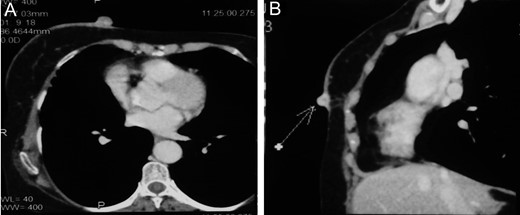

Contrast enhanced computed tomography (CECT) of chest and abdomen showed two enhancing cutaneous nodules measuring 19 mm × 18 mm and 18 mm × 14 mm in medial aspect of right breast with minimal fat stranding noted in superficial subcutaneous plane (Fig. 2). Surrounding skin was edematous. Other findings were lobulated outline of liver and few splenic cysts with no evidence of systemic metastasis. Fine needle aspiration cytology (FNAC) from the nodule revealed clusters and fragments and singly dispersed spindle shaped cells with elongated hyperchromatic nuclei with moderate cellular pleomorphism suggestive of malignant spindle cell neoplasm.

CECT showing enhancing cutaneous nodules in right breast with minimal fat stranding without evidence of deeper tissue penetration (A)Axial section (B)Sagittal section.